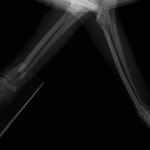

症例3:キルシュナーワイヤーのピンニングによる整復

ペルシャ猫 11ヶ月齢 雄

他院にて左大腿骨遠位の成長板骨折(salter-harrisⅠ型)が認められており、治療相談を目的として来院。当院にて、キルシュナーワイヤーを用いたピンニングにより骨折部位の整復を行いました。術後の経過は良好で、現在も経過観察中です。

術前レントゲン